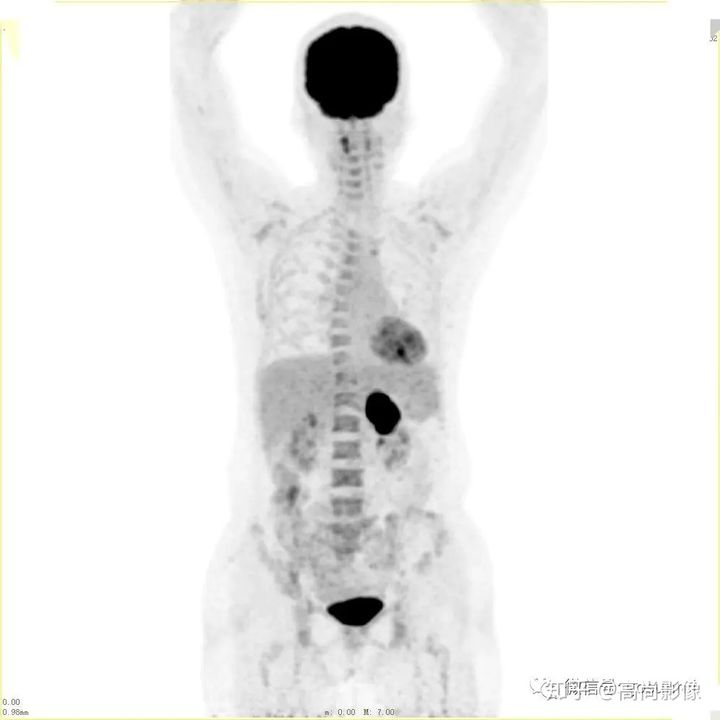

(胸椎骨轉(zhuǎn)移合并病理性骨折)

(右側(cè)髖臼骨轉(zhuǎn)移)

(右肺癌全身多發(fā)轉(zhuǎn)移)

(右肺上葉中央型肺癌)

方大爺?shù)腜ET/CT結(jié)果強烈提示肺癌伴全身多發(fā)轉(zhuǎn)移,已經(jīng)失去手術(shù)機會,但仍有繼續(xù)化療的機會。